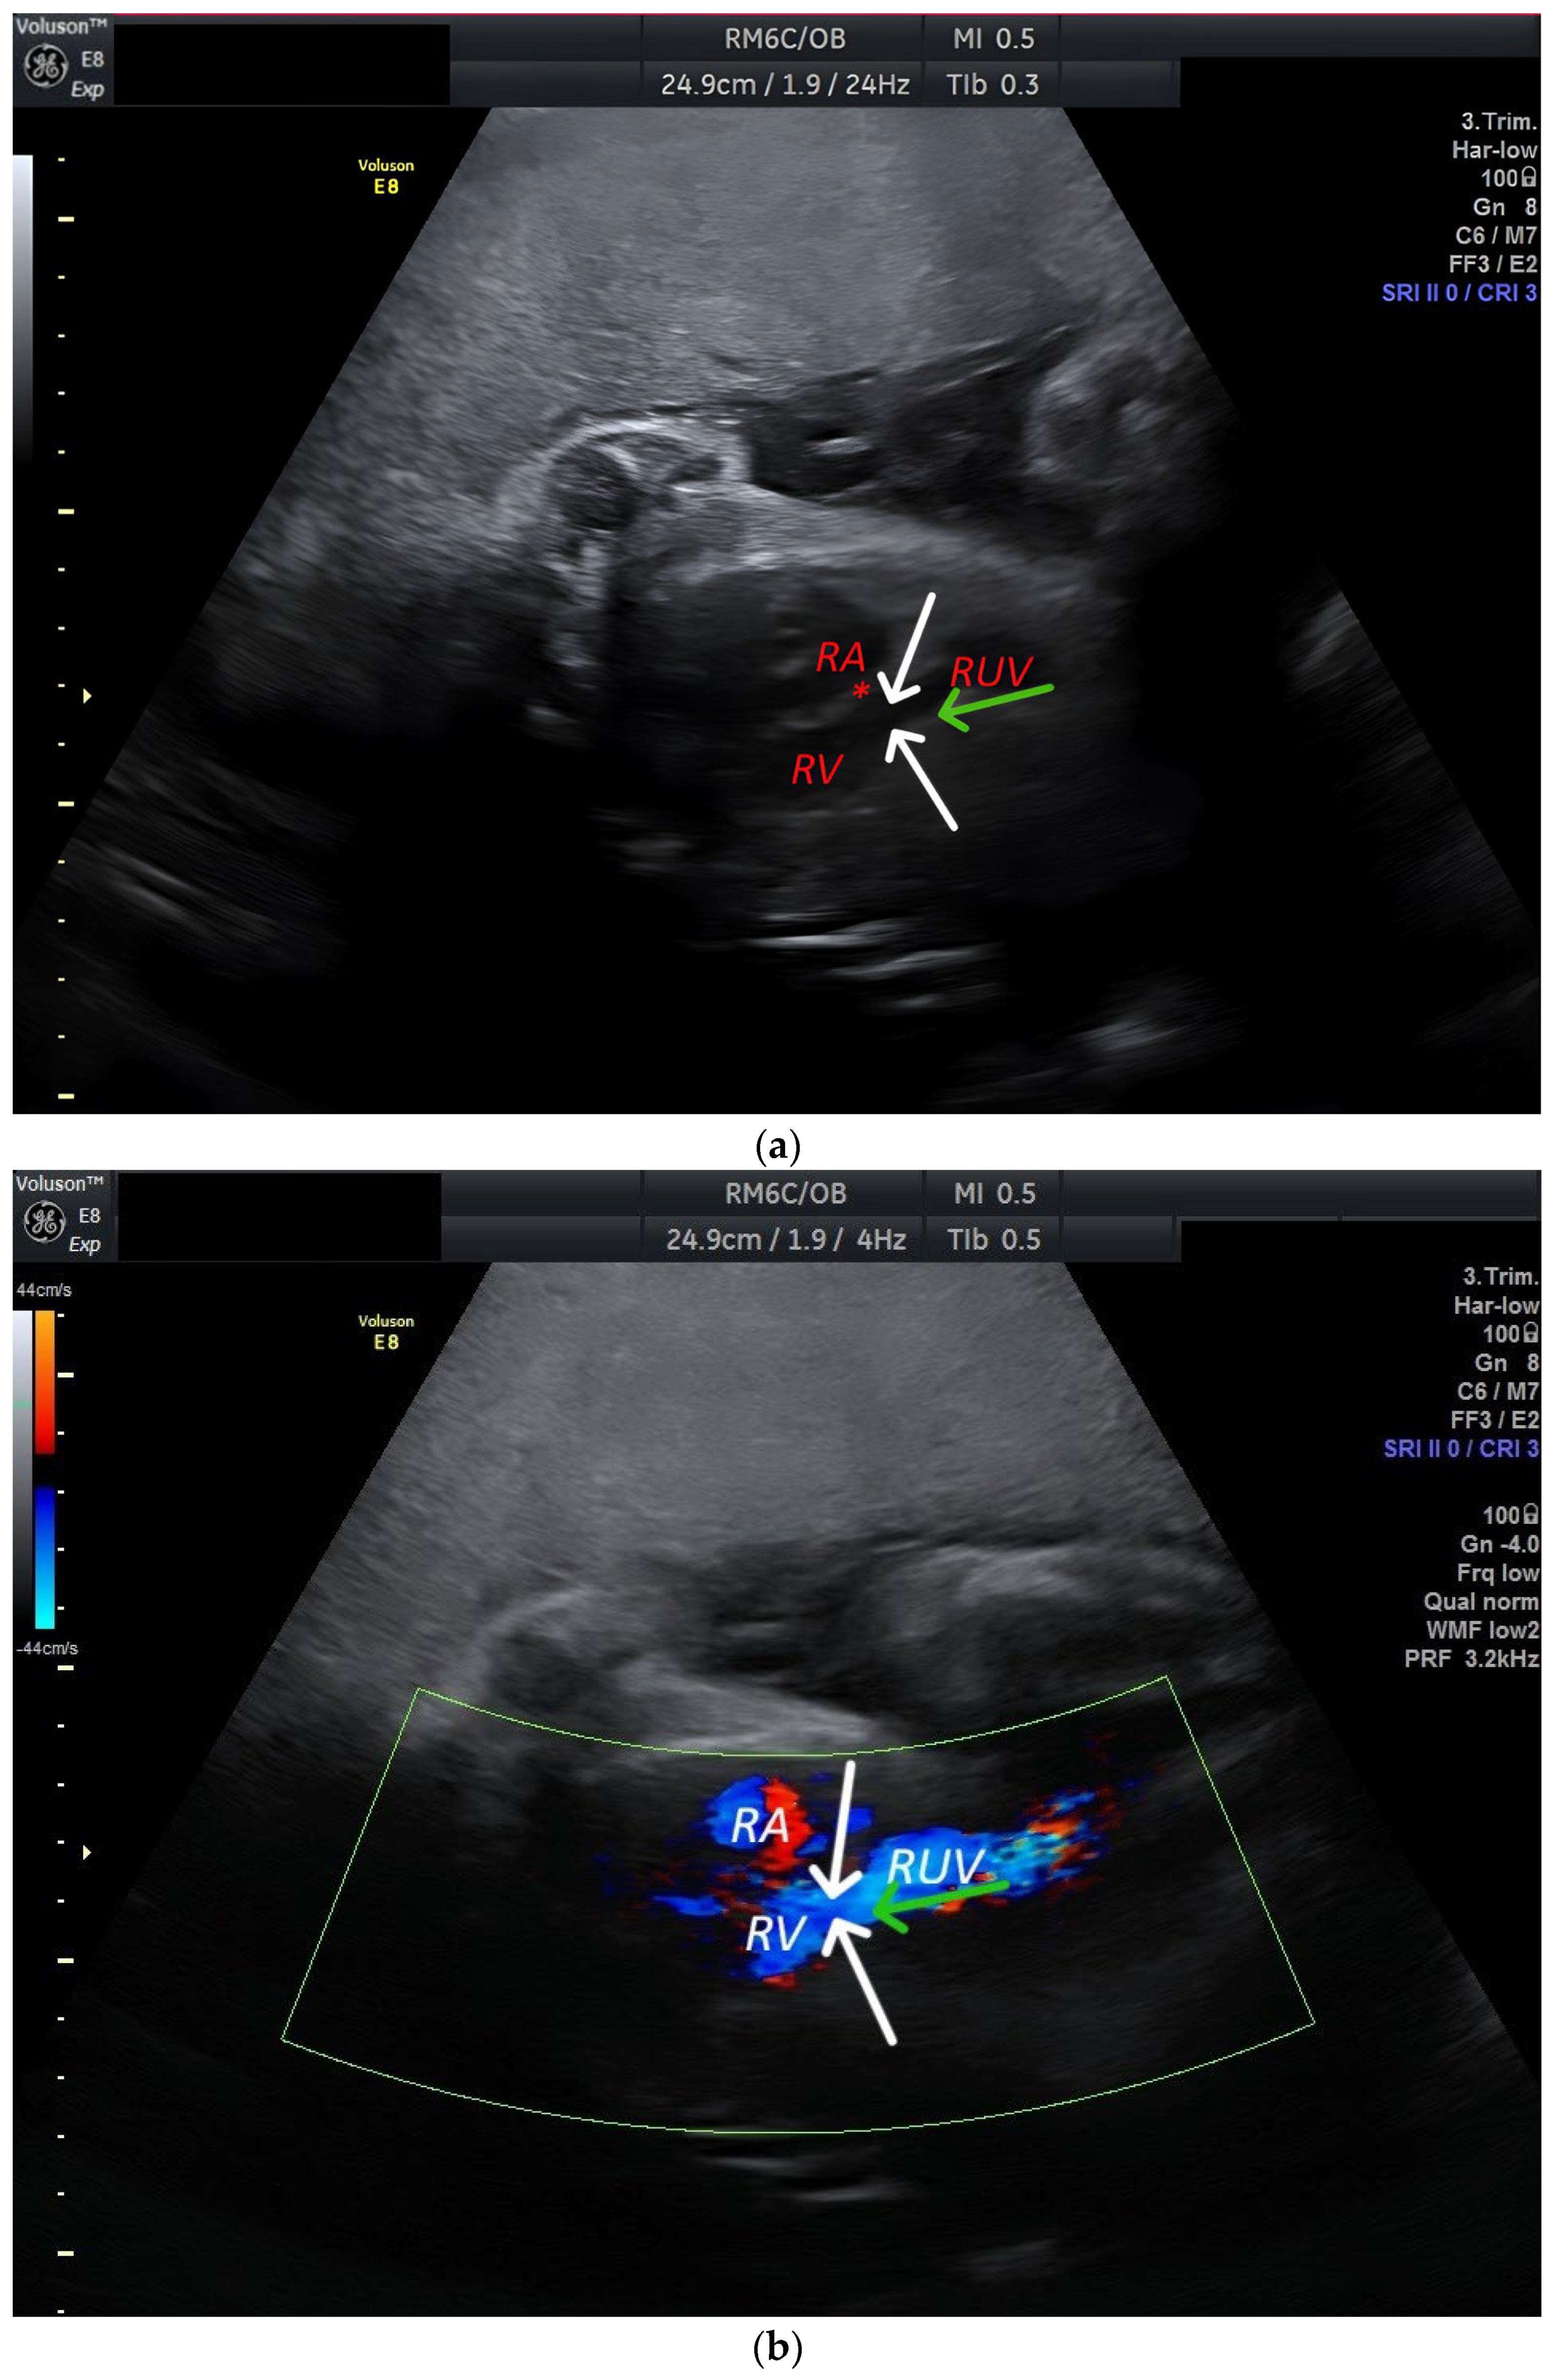

2. Case Report